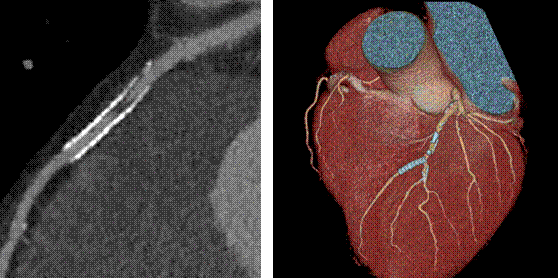

新技術(shù)介紹四:高心率冠脈成像、高清成像

此例為心率83~88bpm,冠狀動脈成像優(yōu)異

寶石能譜CT突破了以往64排CT冠脈掃描時對心率的苛刻要求,增加了患者的接受度,簡化了冠脈CTA成像流程。

高清模式清晰顯示支架術(shù)后再發(fā)斑塊形成

高清模式突破了傳統(tǒng)CT對支架內(nèi)斑塊觀察的難點(diǎn),能夠提供冠脈支架內(nèi)腔的高清圖像。